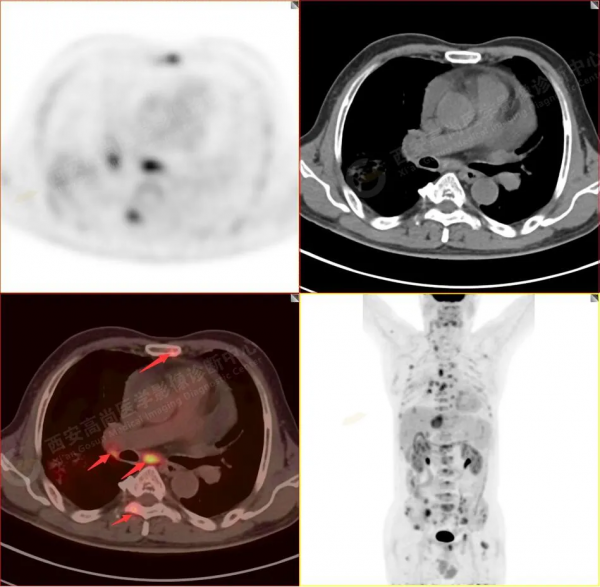

1.以下為肺內原發灶

1.右肺中葉內側段軟組織結節,呈淺分葉狀,邊緣可見毛刺及胸膜牽拉徵,呈FDG代謝異常增高,考慮為周圍型肺癌。

2.雙肺內瀰漫性分佈大小不等實性小結節灶及粟粒狀高密度影,均未見FDG代謝明顯異常增高,均多考慮為癌性淋巴結炎及轉移性病變。

3.右側頸部(Ⅱ-Ⅴ區)、右側腋窩區、右側肺門及縱隔(1R、1L、2、4、6、7組)、肝門區多發腫大淋巴結,呈不同程度異常增高,均考慮為淋巴結轉移。

4.肝S4、8段團塊狀及結節狀低密度病變,以S4段病變為著,呈不同程度FDG代謝異常增高,考慮為肝多發轉移。

5.右側肱骨上段、左側肩胛骨、右側鎖骨胸骨端、胸骨、雙側多發肋骨、脊柱多發椎體及附件、雙側髂骨、雙側髖臼、雙側恥骨、雙側肱骨上段多發成骨性病變,呈不同程度FDG代謝異常增高,考慮為多發骨轉移瘤。

以上病變符合:T4N3M1c,ⅣB期(UICC/AJCC,2018年第8版肺癌TNM分期)。